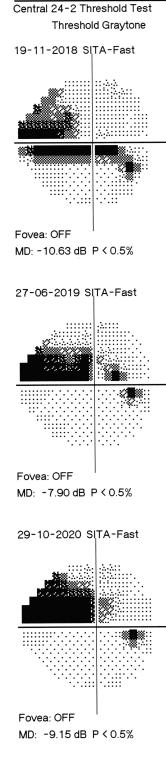

EDITORIAL TEAM